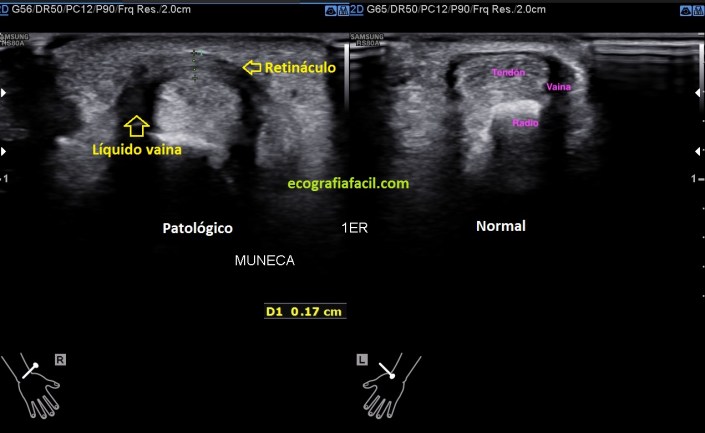

En esta imagen 3 ves un corte axial, o eje corto, del compartimento 1, donde no se objetiva correctamente el tabique separador de los tendones en la zona patológica, donde ves el retináculo engrosado, con líquido en la vaina, compara con la apariencia normal contralateral y almacena en tu memoria…